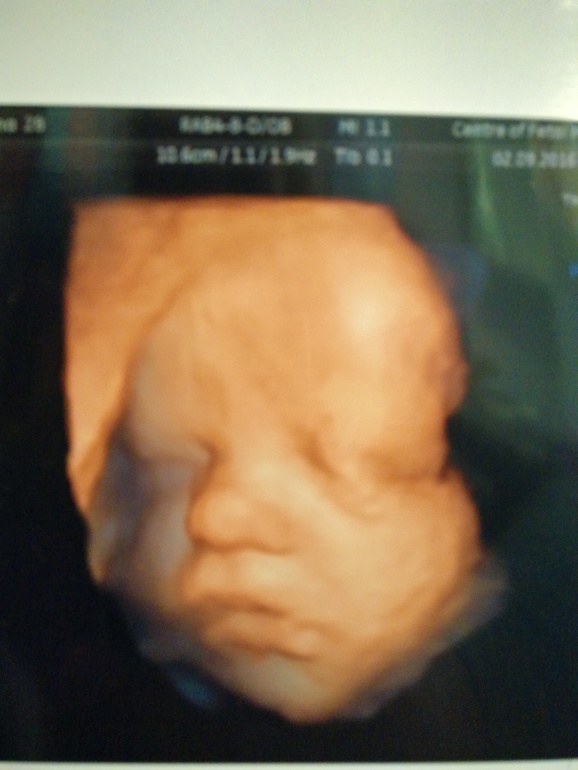

Всё о нашей беременностиМалыш давно уже лежит головкой вниз. Молодчина, мамуле помогает, поскольку плацента в краевом так и осталась, а он её головушкой поджимает, а то бы ножками колотил....что не есть хорошо. Весит на 31+6 1762 грамма. К ПДР предполагают 3300-3400. Вот вам и гестационный сахарный диабет, ну как я и предполагала, что все это....уж слишком натянуто в моём случае. А они:"Вы что?! Обязательно диета!!! Крупный плод будет! Аааа!!!!"Я только улыбаюсь и киваю, и пиццу параллельно заказываю ;) Доктор сказала, что волосатым будет, по УЗИ косы разглядывали)) Вообщем, все у нас хорошо! Фоточку прилагаю. Правый глазик открыт, а левый ну не получился))) P.S. На фото я примеояю новую пеленочку на котэ, морда у нее при этом огонь)))))

Я смотрю коте и детские игрушки примеряет)) надо же и личико как видно хорошо, это 3д?